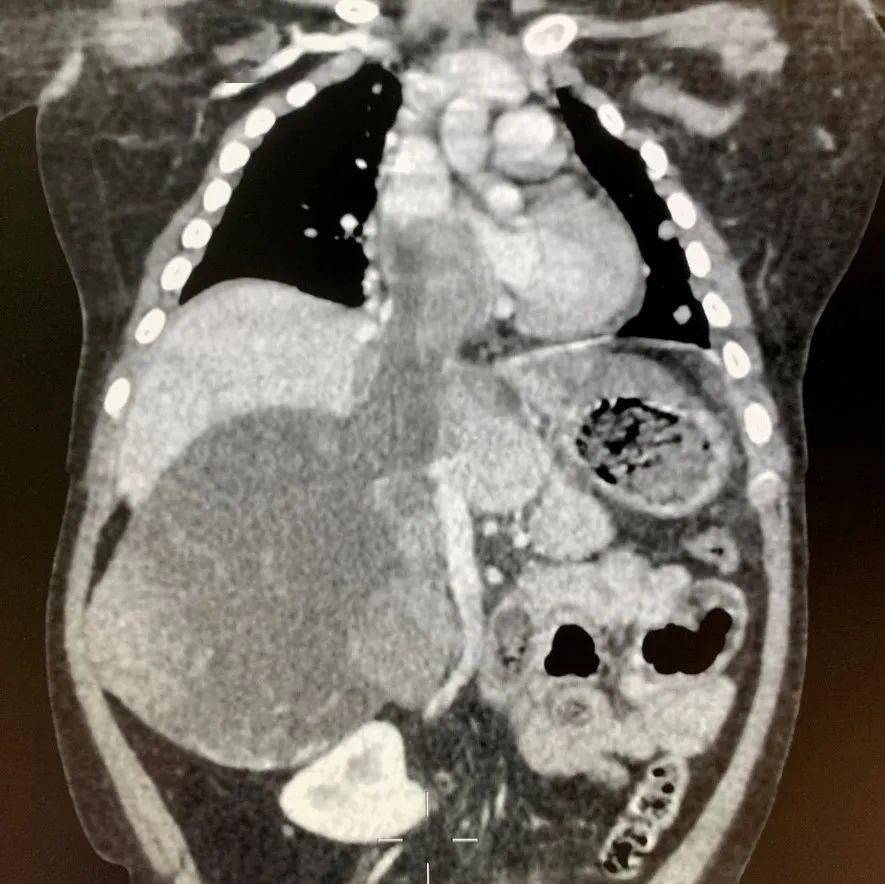

还有一部分患者合并门静脉及下腔静脉内瘤栓 , 肿瘤组织进入大血管内形成栓子 , 甚至在血管内一路上行长入心脏中 , 术中需要在切除肿瘤的同时取出瘤栓 , 必要时需要和心脏外科一起联合手术 , 同时切除腹腔内的肿瘤、血管内的瘤栓以及心脏内的瘤栓 。

肿瘤自下腔静脉内上行长入右心房 , 与心脏外科一起联合手术